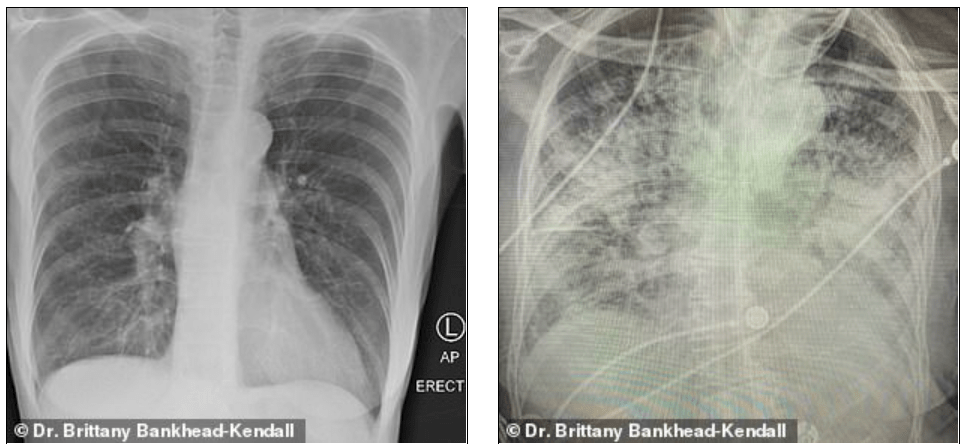

- Doktorka Britany Bankhead-Kendall prednedávnom zverejnila tri snímky pľúc

- Snímky zdravého pacienta boli tmavé, čo dokazuje, že dokáže vdychovať normálne množstvo kyslíka

Bankhead-Kendall je úrazová lekárka, ktorá sa s pozitívnymi pacientmi stretáva od úplného začiatku pandémie. Tvrdí, že pľúca tuhého fajčiara nie sú ani zďaleka také postihnuté ako pľúca osôb, ktoré prekonali koronavírus.

Podľa lekárky sú röntgenové snímky pľúc fajčiarov trochu zahmlené, no snímky pľúc postihnutých koronavírusom sú takmer ciele biele. Zároveň je na nich viditeľné zjazvenie a nedostatok kyslíka, ktorý má putovať do ďalších orgánov.